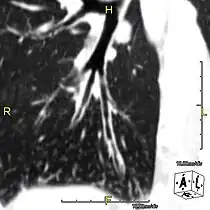

CT image showing situs inversus. The liver is normally on the right side of the body and the spleen on the left, they are switched in this patient with situs inversus.